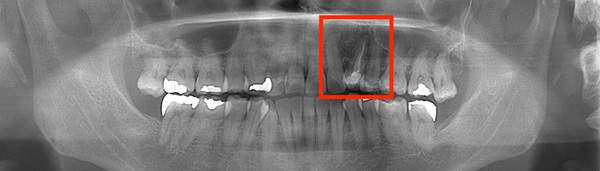

左のレントゲンでは破折したかどうかはわからないが、虫歯になっている部分をとっていくと歯が割れているのがはっきりとわかりました。

数年前に歯の根の治療をうけたにもかかわらず、中で細菌が繁殖し、膿が溜まってしまうことがあります。これを治すには感染根管処置が必要になります。こちらの画像が膿が溜まってしまったものになります。黄色線が歯のラインで、青が膿になります。

根の先端に膿が溜まっています。